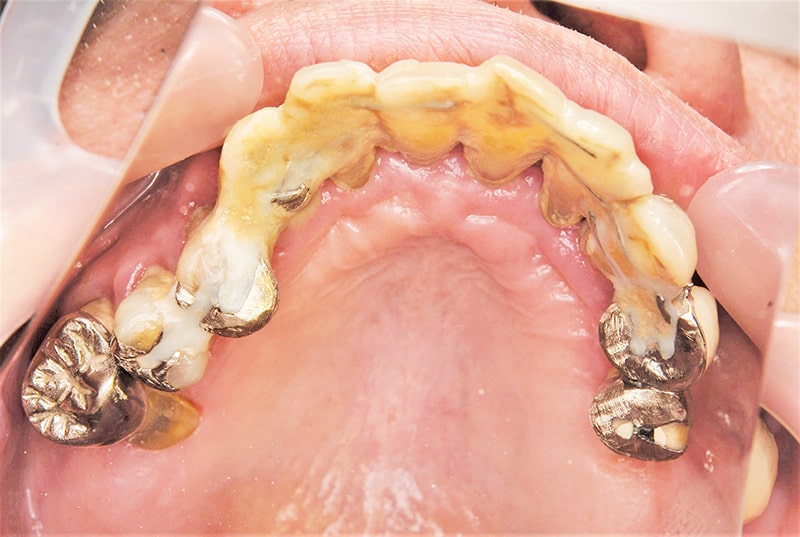

症例3【60代女性】主訴 審美障害・義歯がわずらわしい

治療前

治療後(3年経過)

治療後

※説明

主訴 上下の部分義歯が煩わしい、しっかり奥歯で噛めないと訴え来院。

上顎前歯部、左上臼歯部にはブリッジが装着されていて、支台歯に負担がかかっており、力学的配慮設計を重視し、固定制のインプラントを提案。

前歯部、小臼歯部には、造骨、歯肉移植も含めた幅の確保をし、永続性のある土壌作りを行った。

免荷期間中は、QOLを損なわない為に、ミニインプラント(即時荷重)を埋入、オペ当日に仮歯を装着し、咀嚼可能にした。

最終補綴物装着までの期間は、約8ヶ月を要した。ジルコニア(レイヤリング法)を装着。

リスクとしては、外科的侵襲がある。デメリットは、保険外診療の為、経済的負担がある。

費用 501万 (オペ・ミニインプラント・人工骨・歯肉移植・仮歯・採血による濃縮血小板生成・最終補綴物まで含む)